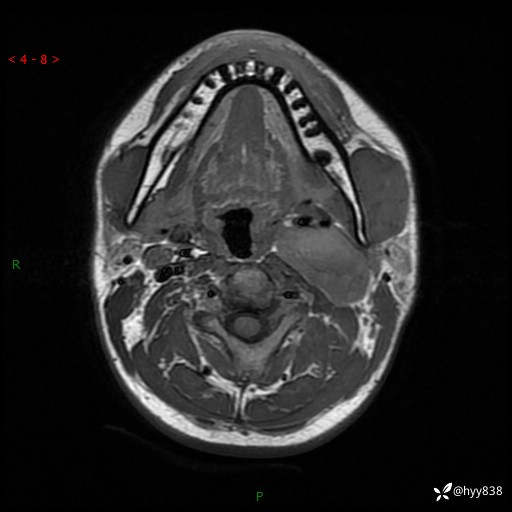

年轻小伙,发现左侧颈部肿物3年余,逐渐增大---结果公布~

现病史:患者约3年前因感冒发现左侧颈部长一肿物,约半个鸡蛋大小,无明显疼痛及其他不适,一直未行特殊处理。3个月前发现左侧颈部肿物变大,随后至当地市第二人民医院耳鼻喉科行左侧颈部彩超示:左侧颈部囊实混合性包块;喉部MPR示:左侧胸锁乳突肌内前方占位,累及左侧喉旁间隙,建议增强扫描。建议手术治疗。患者考虑。随后至我院肿瘤科就诊,行细胞学穿刺示:考虑血管源性肿瘤可能,建议进一步检查。建议至我院口腔科就诊,行颌面部MRI示:左侧颌下腺后方团状异常信号灶,建议增强。建议手术治疗。为求进一步治疗,门诊以“左侧颈部肿物”收入院。 起病以来,患者神志清、精神良好,饮食睡眠良好,大小便正常,体重未见明显变化。

颈部MRI平扫+增强